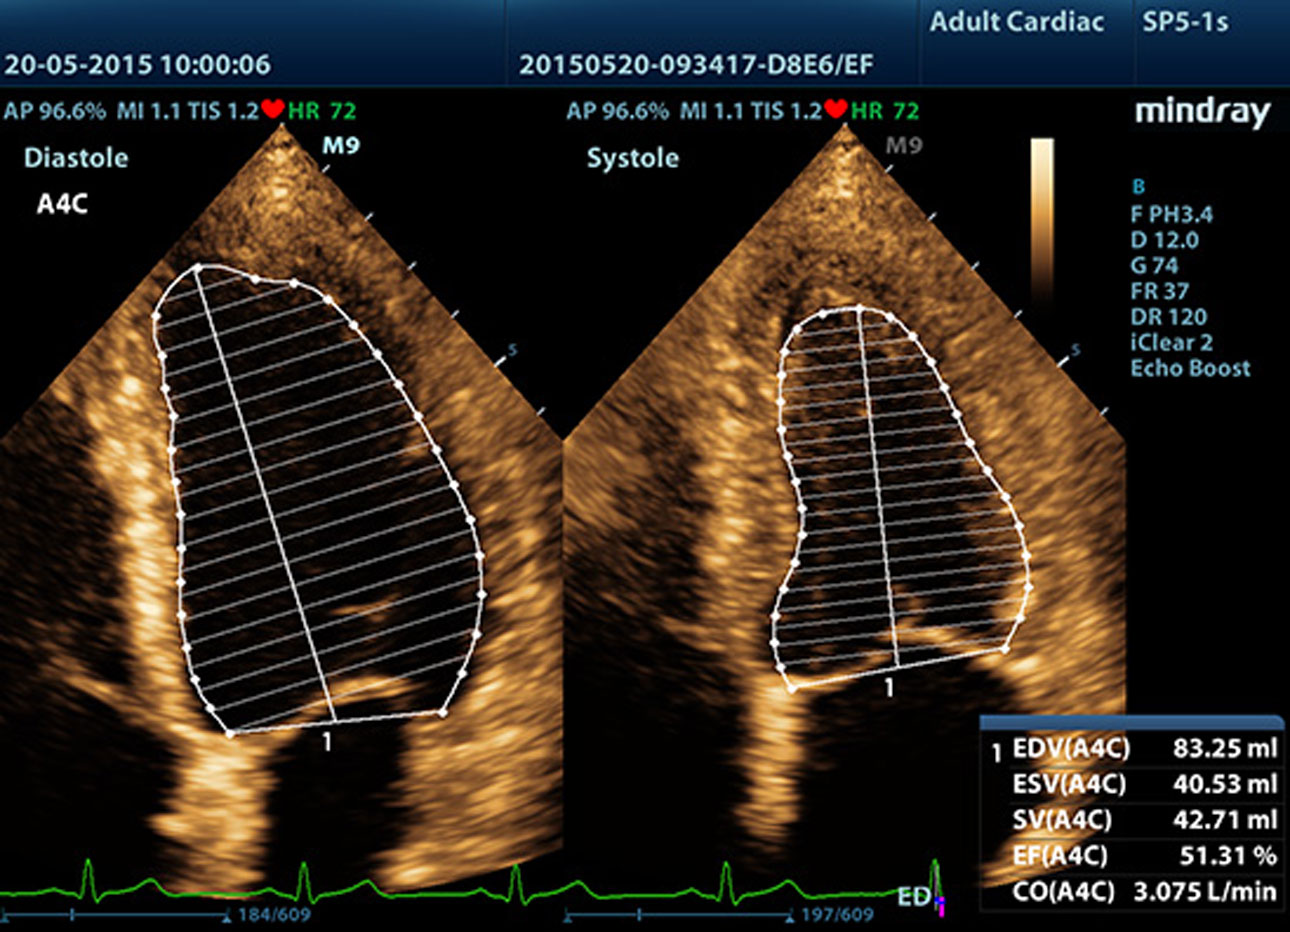

Fracción de eyección automática (AutoEF)

Una forma inteligente de analizar las 2D para reconocer automáticamente los niveles diastólicos/sistólicos y generar la estimación diastólica, el volumen diastólico, la fracción de eyección (EDV/ESV/EF), etc. resultantes del método Simpson.